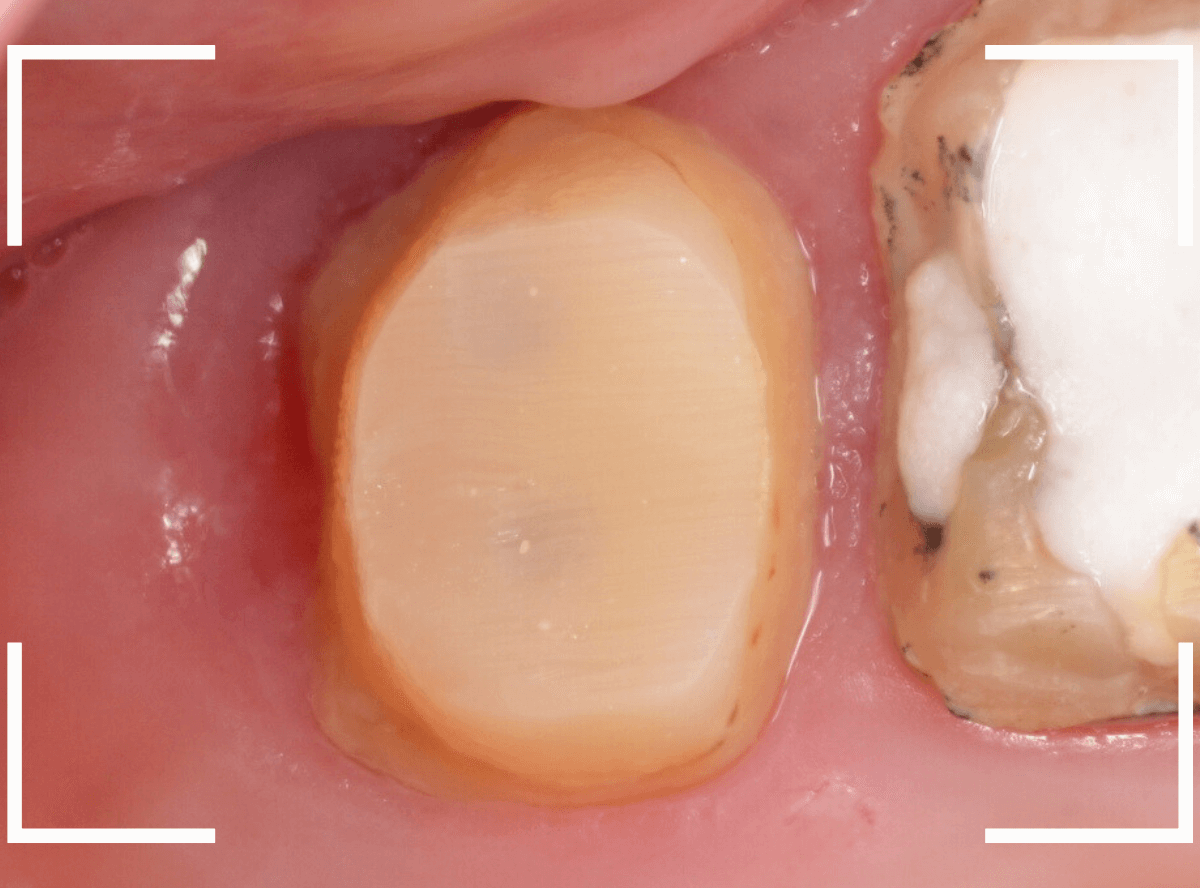

ファイバーコアをsetしてしばらく経過観察したところです。

まだ、少し歯肉の炎症が残っていますが、かなり綺麗になってきました。

歯ブラシでのお手入れを頑張っていただければ、もっと歯の周りの歯肉が引き締まってきますので、それを待って最終のさし歯をお作りする予定です。

ファイバーコアをsetして、しばらく経過観察したところです。

隣の歯との間の歯肉も綺麗になったのが確認できるかと思います。

良いさし歯をお作りできる環境になりました。

最終のさし歯が入ったところです。

ほとんど調整もなく、ぴったりと周りの歯に合わせる事ができました!